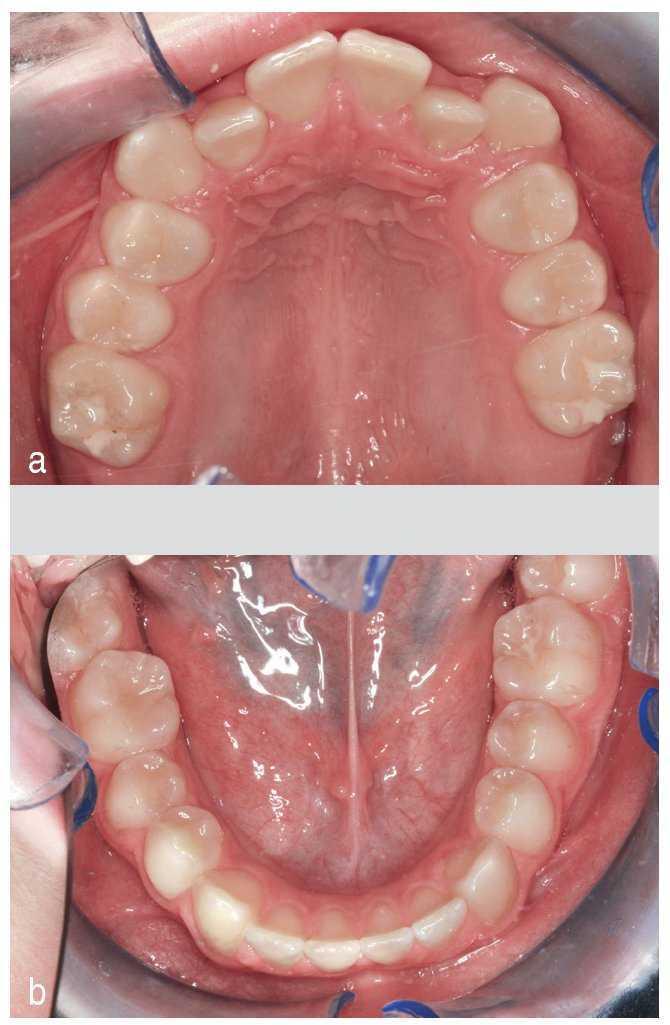

Se trata de un paciente con clase esquelética III y clase I dental3,5. Presentaba dientes anterosuperiores situados en mordida cruzada, desviación funcional y el apiñamiento correspondiente. La arcada inferior ofrecía una imagen relativamente armoniosa (figs. 1 a 5).

Figura 1. Mordida cruzada anterior.

Figura 3. Apiñamiento en el maxilar, arcada inferior armoniosa.